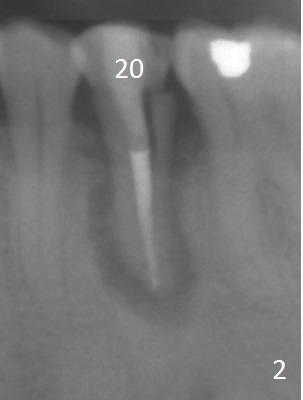

A 53-year-old man (probably bruxer, long roots) has 3 missing teeth (Fig.1 #14,18,29) and 1 fractured tooth (Fig.2 #20). The fractue is associated with deep buccal pockets. The buccal plate is most likely defective. After extraction (Metronidazole), start osteotomy lingual and mesial (Fig.3 red long arrow) to reduce damage to the Mental Loop (Fig.4 red dashed line). Damage to the Incisive Canal (yellow dashed line, the continuum of the Inferior Alveolar Canal after giving off the Mental Loop) is less significant. Since the defect is long, use the longest implant and place it deep. A long abutment (7 mm, green) with 5 mm cuff (pink) is required. To have sufficient buccal gap for bone graft and probably membrane, the smallest two-piece implant is necessary (3.8 mm).